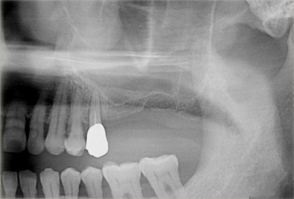

サイナスリフト

上顎には上顎洞と呼ばれる空洞が存在します。

この上顎洞から歯の部分までの骨の高さが不足している場合に、人工骨や自身の骨(自家骨)を移植することにより、インプラント埋入するために必要な骨の厚みを作り出す方法です。

インプラント埋入前にサイナス部分にGBRを行い、骨が出来上がるのを待ってからインプラント治療を実施。

- 上顎臼歯部の67欠損となり、上顎洞までの距離が不足したためインプラントの早期埋入が不可能であった

- 上顎頬側よりラテラルウインドウ法で上顎洞底挙上術を行い2本のインプラントの埋入を行なった